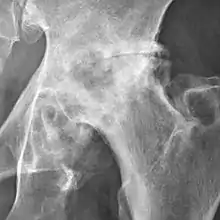

Hip

The most commonly used radiographic classification system for osteoarthritis of the hip joint is the Kellgren–Lawrence system (or KL system).[6] It uses plain radiographs.

| Grade | Description |

|---|---|

| 0 | No radiographic features of osteoarthritis |

| 1 | Possible joint space narrowing (normal joint space is at least 2 mm at the superior acetabulum)[7] and osteophyte formation |

| 2 | Definite osteophyte formation with possible joint space narrowing |

| 3 | Multiple osteophytes, definite joint space narrowing, sclerosis and possible bony deformity |

| 4 | Large osteophytes, marked joint space narrowing, severe sclerosis and definite bony deformity |